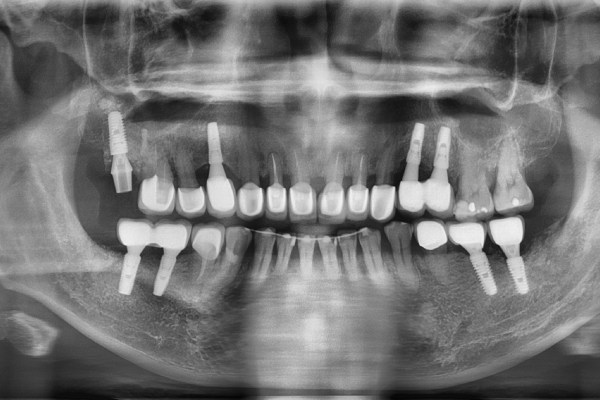

這是一個非常難得專業技術,除了診所是否有高科技設備、病人體質等因素,最重要的是執刀的醫師是否具有相當豐富的臨床經驗,還有診所內的其他領域醫師一起協同治療的能力,將一個療程可能原本要分3~4次才能完成的手術,有技巧地將雷射牙周治療、拔牙、補骨、植牙合併一次完成,可以減少很多等待時間的浪費。

病患原本因牙周病造成齒列不正,經評估後,將下顎的牙齒採用矯正方式,其餘不能救的牙齒採用拔牙、補骨、植牙一起處理,當天也同時進行雷射牙周病治療完成。

重建前

重建後